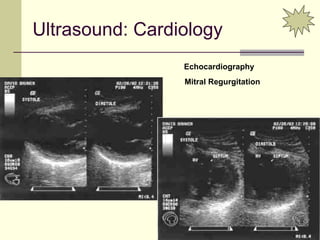

Ultrasound: Cardiology

Echocardiography

Mitral Regurgitation